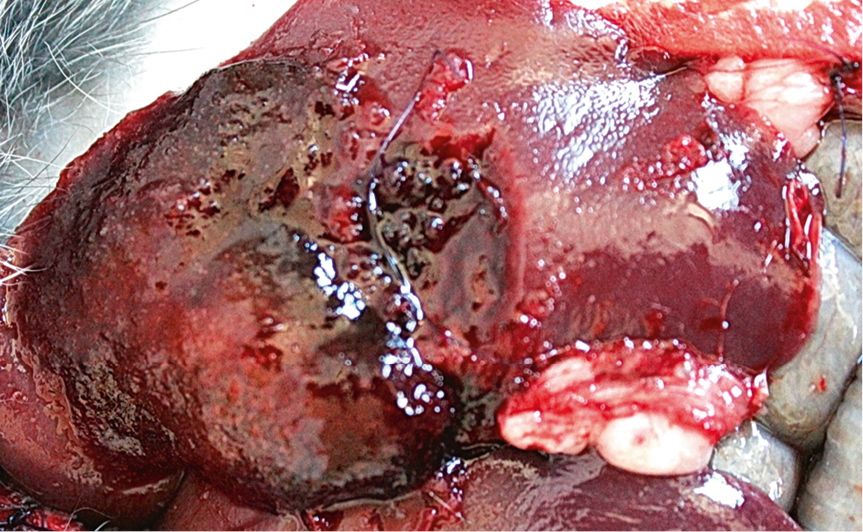

На основе полученных данных при аутопсии удалось выявить наиболее характерные патоморфологические изменения, имевшие место при испытании внутриполостных МГС. Так, высокая гемостатическая активность всех препаратов была связана с хорошей адгезивной способностью опытного МГС к источнику кровотечения (рис. 3).

Рис. 3. МГС «0401» при наблюдении в течение 180 мин. Эффективный гемостаз. Основная масса препарата пропитана кровью

Масса опытного препарата увеличивается в 1,5–2 раза за счет сорбции крови. Наиболее выраженный гемостатический эффект был у образца МГС «0103-20» (рис. 4).